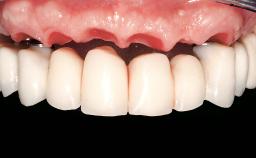

Immediate Loading of Eight Implants in the Maxilla and Six Implants in the Mandible and Final Restoration with Three-Unit and Four-Unit FDPs

Extensive scientific evidence has confirmed that immediately loaded implants with fixed full-arch provisional restorations can osseointegrate with success rates similar to conventionally or delayed loaded implants. A number of immediate-provisionalization techniques for edentulous jaws have been described. Some protocols differ when it comes to prefabricated provisional templates versus complete denture conversion; intrasurgical impressions versus direct relining; and cemented versus screw-retained provisional restorations. In this context, complete-denture conversion has been proposed for either intrasurgical impressions or direct relining. Another possibility is the utilization of a prefabricated provisional to be adapted either in the mouth (by direct relining) or in the laboratory (on a working model obtained from an intrasurgical impression).

Prosthesis Type FDP

Defining Characteristics Fully edentulous upper jaw to be rehabilitated with an implant-borne fixed dental prosthesis